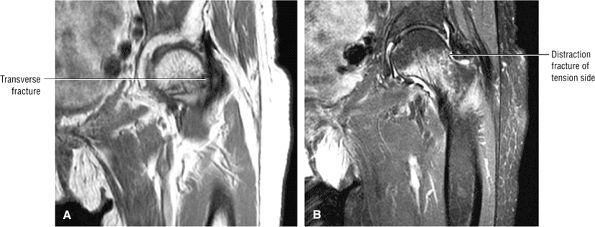

A hypointense fracture line parallel to the subchondral plate (high-resolution imaging is necessary for visualization)

Marrow edema, which can be seen as early as 48 hours after the onset of clinical symptoms

Most cases actually represent subchondral femoral head stress fractures, which can be appreciated on small-FOV images.

A narrow line of sclerosis associated with a subchondral stress fracture

FIGURE 3.98 ● A 40-year-old male patient with subtle subchondral stress fracture easily mistaken for transient osteoporosis. (A) Coronal T1-weighted image. (B) Coronal FS PD FSE image. (C) Sagittal FS PD FSE image.